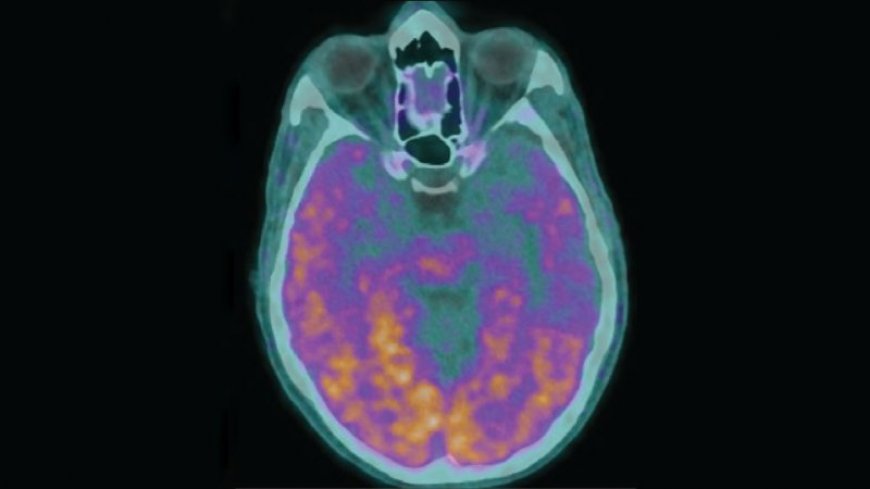

Under extremely rare circumstances, it appears that Alzheimer’s disease can be transmitted between people. Five people who received contaminated injections of a growth hormone as children went on to develop Alzheimer’s unusually early, researchers report January 29 in Nature Medicine.

Most cases of Alzheimer’s disease arise spontaneously in older people (in the United States, for instance, about 1 in 9 people aged 65 and older have the disease). That’s part of what makes these newly described cases of Alzheimer’s so unusual. Symptoms started early for these five people with Alzheimer’s — between ages 38 and 55 — and in three for whom genetic data were available, researchers ruled out the presence of mutations known to cause early-onset forms of the disease.

It turns out that those batches held another problem. In an earlier study, Collinge and his colleagues had found higher-than-expected levels of amyloid-beta in the brains of four people who had died with CJD. Accumulation of the sticky protein is a hallmark of Alzheimer’s and, in these cases, a worrisome signal that perhaps some of these proteins had been transferred, along with prions, from donors (SN: 9/9/15). A-beta from some of the hormone batches could spread in the brains of mice, suggesting that the protein behaves in some ways like an infectious prion, the researchers reported in 2018 (SN: 12/13/18).

Beyond these rare circumstances, the results may hold clues about how Alzheimer’s disease can take hold in the brain, and whether A-beta, like a prion, incites other versions of A-beta to misfold. Untangling the details of how various forms of A-beta spread “lies ahead,” Collinge said. “A great deal more research needs to be done.”